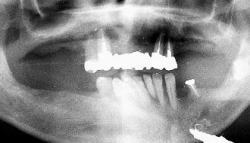

| 治療前 | 治療後 |

|---|---|

| 上顎はいつ抜けてもおかしくない状態であったため、直ちにAll-on-4を施術しました。 下顎も重度の歯周病で状態は良くありませんでしたが、患者様の希望もあり、抜歯せず、現在経過観察中です。 |